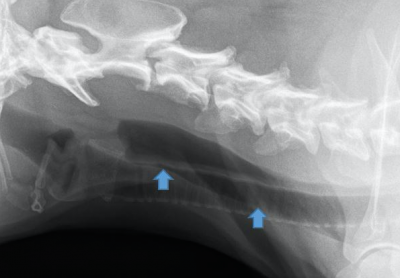

According to the principles of veterinary orthomanual medicine, vertebral misalignments are associated with intervertebral disc disease in dogs. Manual correction of these vertebral misalignments are...